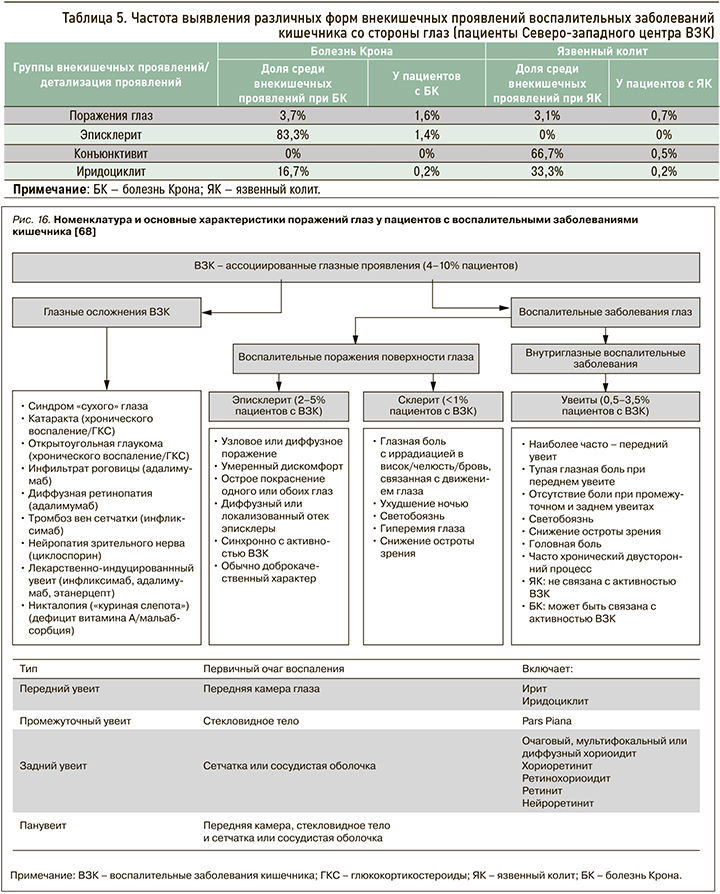

Орган зрения находится на 3-м месте после суставов и кожи по предрасположенности к аутоиммунному воспалению в сочетании с ВЗК. По мировым литературным данным, до 7% пациентов с ВЗК когда-либо имели поражения глаз, самыми частыми из которых были эписклериты, склериты и передние увеиты [69]. Намного реже отмечаются васкулит сетчатки, папиллит, инфильтраты роговицы, миозиты и поражение зрительного нерва [69]. В педиатрической когорте внекишечные глазные проявления встречаются значительно чаще, чем у взрослых. Более высокий риск развития этих внекишечных проявлений имеет место при болезни Крона, чем при язвенном колите. Также поражение глаз обычно ассоциировано с наличием кожных или суставных внекишечных проявлений (рис. 16) [69].

По данным регистра Северо-западного центра ВЗК, глазные внекишечные проявления отмечаются не так часто, как суставные и кожные симптомы: у 0,7% больных с язвенным колитом и вдвое чаще при болезни Крона (1,6%) (табл. 5).

Эписклерит – это воспаление соединительной ткани между склерой и конъюнктивой, которое выступает самым частым глазным проявлением ВЗК и напрямую связано с активностью заболевания [70]. Склерит, наоборот, редкое проявление ВЗК, встречающееся менее чем в 1% случаев [70]. Опасность его заключается в том, что при отсутствии адекватной терапии заболевание может привести к пожизненной потере зрения.

Под увеитом подразумевают воспаление пигментированной оболочки глаза, которое, в отличие от поражения склеры и эписклеры, слабо ассоциировано с активностью заболевания (рис. 17). В исследовании швейцарской когорты пациентов с ВЗК это осложнение выявлялось в 2 раза чаще при активной болезни Крона по сравнению с ремиссией (12,2 и 5,2% соответственно), однако при язвенном колите такой корреляции не было (4,1 и 3,5% соответственно) [46].